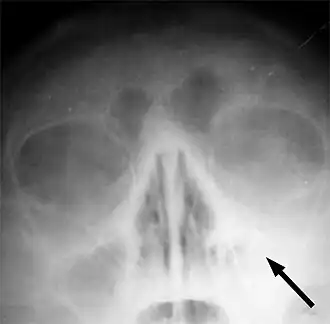

![]() Radiografía que muestra congestión de orificio nasal maxilar izquierdo indicado por una flecha. | ||

En la gran mayoría de los casos de sinusitis aguda, el diagnóstico es exclusivamente clínico, y no hay necesidad de realizar exploraciones y pruebas complementarias.[13] En casos con sospecha de complicaciones, que son excepcionales, se pueden realizar exámenes vídeo-endoscópicos, así como un TAC (tomografía axial computarizada) o una tomografía computarizada de haz cónico (CBCT: cone beam computed tomography). Es de destacar que la utilización de los rayos X convencionales para el diagnóstico de las sinusopatías, antiguamente práctica habitual, está actualmente desaconsejada, debido a la alta tasa de fallos que este tipo de examen presenta para los senos faciales. Los fallos de los rayos X convencionales para el diagnóstico de las sinusopatías abarcan tanto falsos negativos como falsos positivos. Por otra parte, en el caso de la sinusitis crónica, hay que tener en cuenta que las celdillas etmoidales representan un importante obstáculo anatómico que restringe en gran medida las posibilidades de los exámenes vídeo-endoscópicos en aquellos pacientes en los que estas no hayan sido retiradas por completo por procedimientos quirúrgicos, es decir, en la gran mayoría de la población. Son necesarios procedimientos como las tomografías computarizadas, que proporcionen imágenes de las zonas a las que no puedan acceder los endoscopios. Las tomografías computarizadas de haz cónico (CBCT) suelen ser empleadas principalmente en otorrinolaringología y en odontología y ofrecen tres ventajas importantes con respecto a las axiales (TAC): En primer lugar las imágenes resultantes pueden ser también tridimensionales en lugar de solamente bidimensionales; en segundo lugar requieren de una dosis de radiación mucho más baja; y en tercer lugar proporcionan una resolución de imagen más alta. Las tomografías computarizadas son en general de especial importancia en relación con los senos paranasales, dado que no son excepcionales los casos de sinusitis crónica que cursan sin hallazgos en exploraciones video-endoscópicas y sin un solo síntoma aparente que se asocie normalmente a una sinusitis, aparte de un decaimiento general. La ausencia de tales síntomas y de cualquier otro hallazgo puede a su vez inducir erróneamente a sospechar problemas mentales o emocionales: existen casos en los que sin la ayuda de un procedimiento comparable al de la tomografía computarizada resulta imposible detectar una sinusitis crónica. En resumen, la sinusitis, si es aguda, suele ser muy fácil de diagnosticar, gracias a sus síntomas; y por el contrario, si es crónica, puede ser extremadamente difícil de diagnosticar, si no es gracias a la tomografía computarizada.